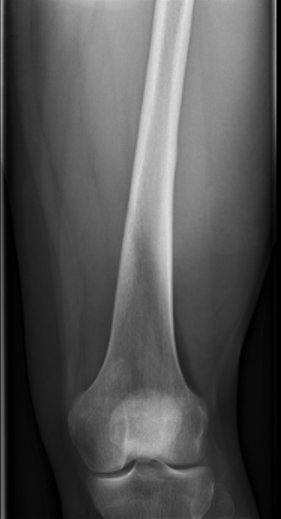

Xray

Often diaphyseal

- diffuse permeative destruction

- can be subtle

Periosteal reaction

- Codman's triangle / onion skinning / sunburst appearance

Pathological fracture with skip lesion

Ewing's distal femur